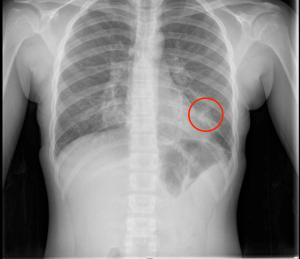

- Puzzler: 14-year-old with asthma, vomiting, and vape use presents with chest pain